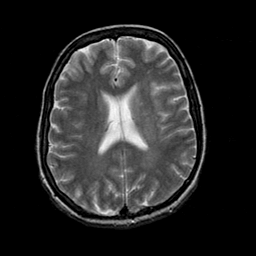

Acute Stroke: T2-weighted MR -- Slice #16

[Home][Help][Clinical][Tour 1] Slice 16